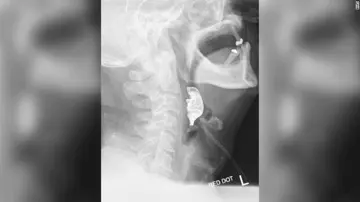

دندان‌هایی که هشت روز در گلو مانده بودند!

یک مرد ۷۲ ساله که دچار مشکلات تنفسی و بلع شده بود، پس از ۸ روز متوجه شد که تعدادی از دندانهای مصنوعی‌ او در گلویش گیر کرده‌اند.